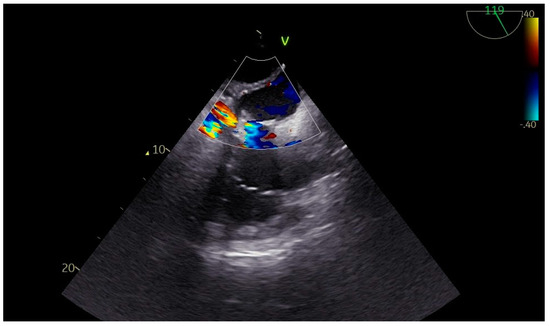

Advanced hemodynamic monitoring as per local protocol was applied with cannulation of the right radial and femoral arteries as well as establishment of peripheral access with two (wide) 16 G cannulae. Baseline invasive blood pressure before induction was 145/60 mmHg. Induction to anesthesia was uneventful without any signs of hemodynamic instability, using balanced anesthetics for the maintenance of general anesthesia too. A central line and pulmonary artery catheter were placed in the right internal jugular vein. Continuous cardiac monitoring and cerebral oximetry monitoring were applied while depth of anesthesia was monitored with the Bispectral Index. Intraoperative transesophageal echocardiography (TEE) was used and confirmed the findings of TTE, especially with a heavily calcified mitral valve annulus (Figure 1). Standard bicaval extracorporeal circulation through sternotomy and mild systemic hypothermia (32 °C) were used. Myocardial protection was made by a combination of antegrade and retrograde cold hyperkalemic blood cardioplegia. Cardiopulmonary bypass time was nearly two hours. The separation from cardiopulmonary bypass was initially smooth with minimal vasopressor support (blood pressure > 85–90/45 mmHg). A few minutes after the protamine administration an episode of profound hypotension caused major hemodynamic instability (blood pressure > 55–60/35 mmHg), which was related to the protamine side effects. However, since it persisted, regardless of the treatment with vasopressors, a thorough reassessment with the TEE was performed. This dynamic investigation revealed an obvious flap fluctuating in the left atrium, suggestive of a dissection flap in the chamber (Figure 2). (The dissection flap size was at least 7.2 cm. There was difficulty in the precise measurement of its dimension because the left atrium roof could not be visualized.) Otherwise, the two new prosthetic valves were well seated without any residual regurgitation (Figure 3 and Figure 4). The most plausible explanation for the presence of the dissection flap was the earnest mitral valve replacement performed in the setting of extensive mitral annular calcification. Hemodynamic stability was achieved with boluses of vasopressors (phenylephrine) and noradrenaline and adrenaline infusions. Since the patient was relatively stabilized under this support, the chest was closed and he was taken to the intensive care unit with a target for systolic blood pressure less than 100–120 mmHg for the first twenty-four hours (Table 1).

Figure 1. TEE preoperative image showing mitral valve calcification with size of 38 mm.